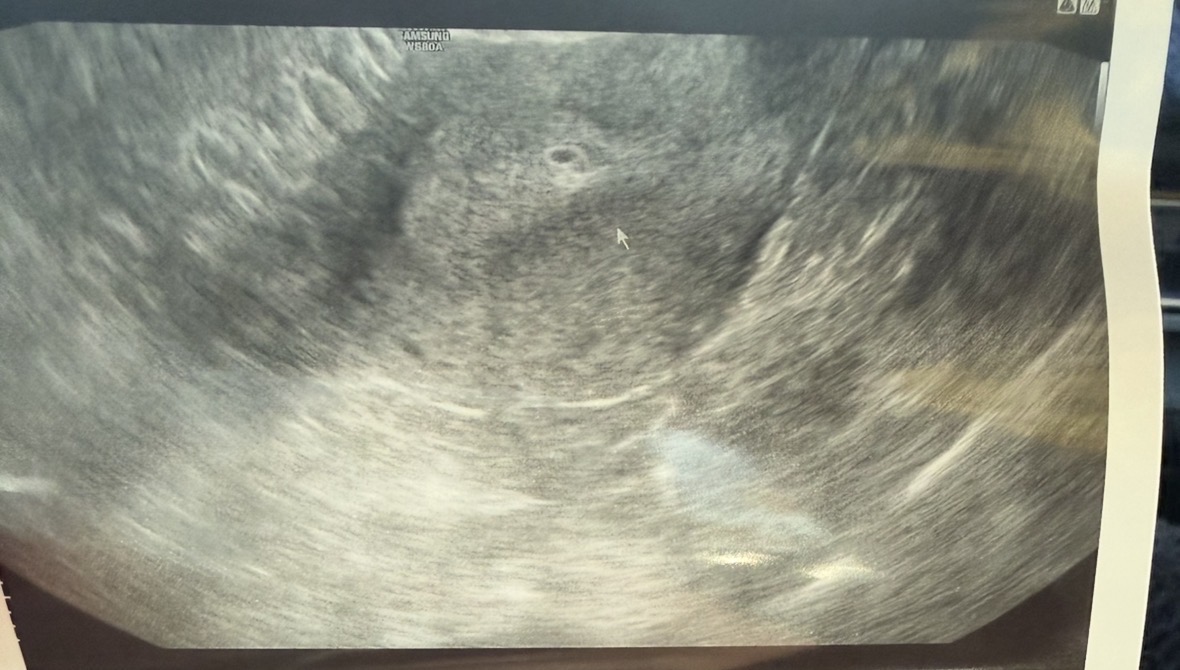

4주5일차로 측정되었네요..

생예때 두줄보고 병원 연락해서 5주차가되어야한다해서 오늘로 날짜 받아서 다녀왔는데 아기집이 너무 작네요.. 4주5일로 확정받았어요..! 배란은 24-25일 추정이라 늦는거겠죠..? 막상 아기집이 작다하니 너무 걱정되서 눈물이 왈칵..